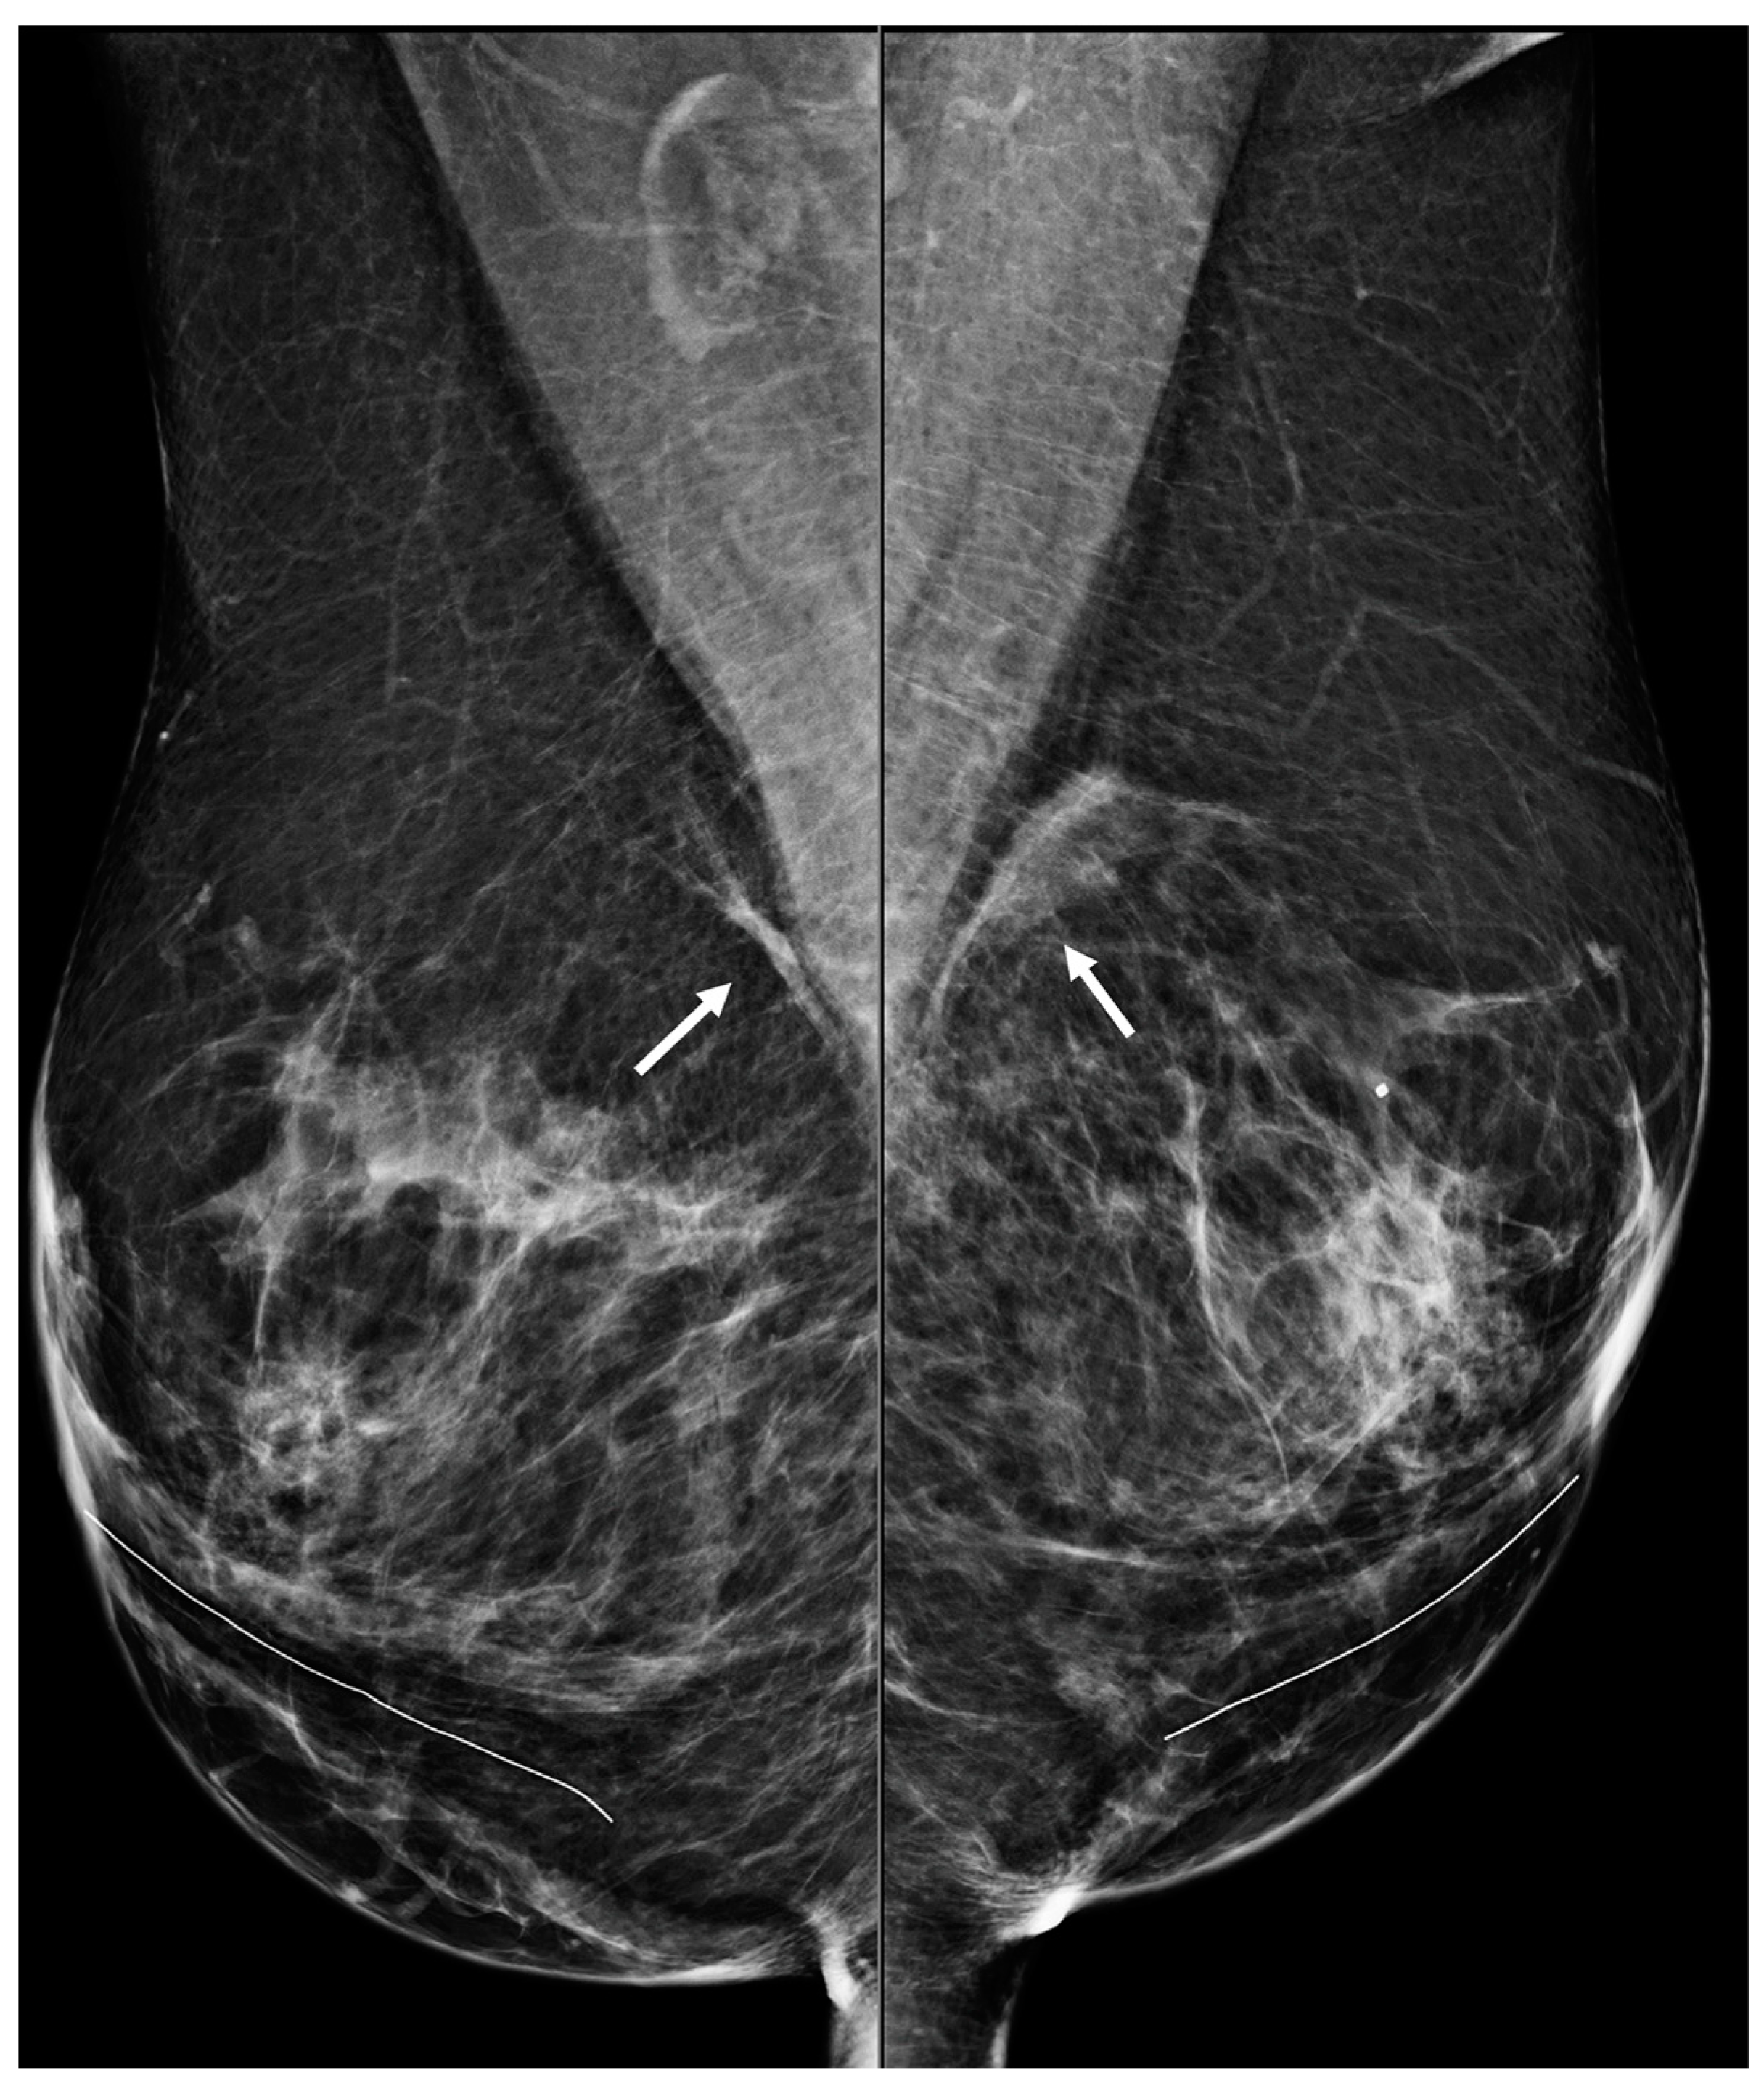

Figure 7. A 50-year-old woman with a history of subglandular silicone implants. Mammography with bilateral MLO views one year after BES demonstrates bilateral linear asymmetries (arrows) in the subglandular region.